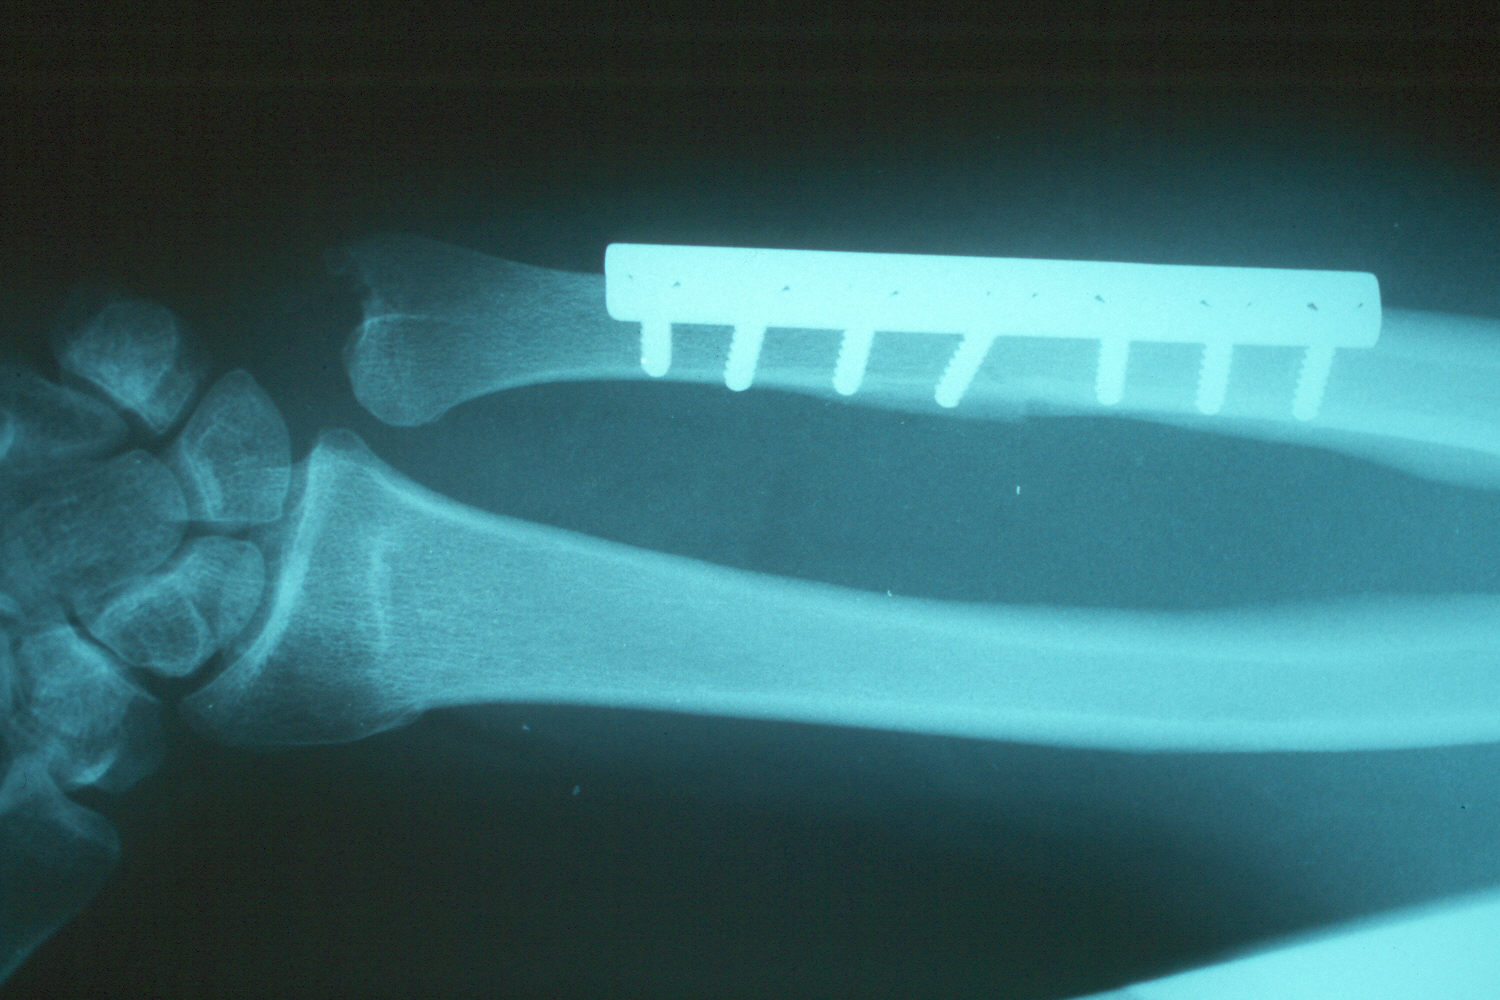

Late result: proper ulnar alignment restored.

The osteotomy and plate position are planned using a seven hole plate with a compression screw positioned obliquely across the osteotomy cut.

Late result - healed.